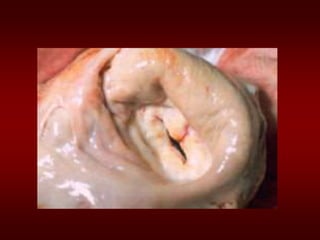

Etiology of Mitral Stenosis

• Rheumatic heart disease: 77-99% of all

cases

• Infective endocarditis: 3.3%

• Mitral annular calcification: 2.7%